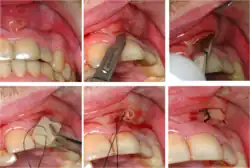

Dental abscesses

A general principle concerning dental abscesses is ubi pus, ibi evacua ("where there is pus, drain it"), which applies to any case where there is a collection of pus in the tissues (such as a periodontal abscess, pericoronal abscess, or apical abscess). The pus within the abscess is under pressure, and the surrounding tissues are deformed and stretched to accommodate the swelling. This leads to a sensation of throbbing (often in time with the pulse) and constant pain. Pus may be evacuated via the tooth by drilling into the pulp chamber (an endodontic access cavity). Such a treatment is sometimes termed open drainage. Drainage can also be performed via the tooth socket, once the causative tooth is extracted. If neither of those measures succeeds, or they are impossible, incision and drainage may be required, in which a small incision is made in the soft tissues directly over the abscess at the most dependent point. A surgical instrument such as a pair of tweezers is gently inserted into the incision and opened, while the abscess is massaged to encourage the pus to drain out. Usually, the reduction in pain when the pus drains is immediate and marked as the built up pressure is relieved. If the pus drains into the mouth, there is usually a bad or offensive taste.